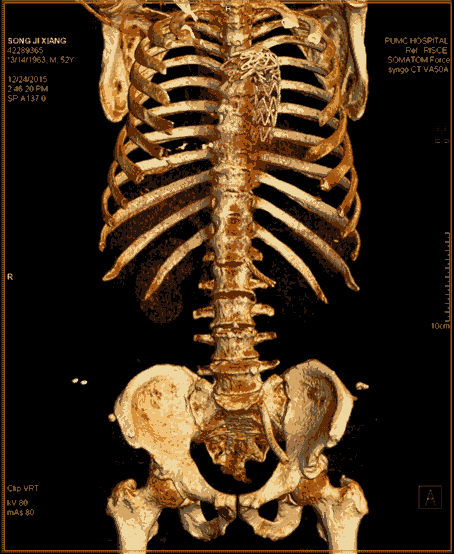

近日,代表當(dāng)前CT最高水平的西門子SOMATOM Force開源CT在滕州市中心人民醫(yī)院正式啟用。Force CT采用全球獨(dú)創(chuàng)的雙球管、雙探測(cè)器結(jié)構(gòu),臨床應(yīng)用領(lǐng)域廣泛,在全身各部位的無創(chuàng)成像方面開創(chuàng)了高端CT應(yīng)用的新紀(jì)元,尤其在冠心病冠脈成像方面有無可比擬的優(yōu)勢(shì),其操作便捷、安全無創(chuàng)和綠色環(huán)保引領(lǐng)著業(yè)內(nèi)的標(biāo)桿和典范,被稱為“窺心神器”。

Force CT以超低的輻射、精準(zhǔn)的診斷,開創(chuàng)了CT安全篩查的新時(shí)代。

SOMATOM Force是全新的第三代雙源CT,革新了球管、高壓發(fā)生器、探測(cè)器、數(shù)據(jù)采集系統(tǒng)、重建系統(tǒng)等一系列影像鏈,定義了一個(gè)無與倫比的 CT 性能等級(jí),開辟了全新的CT影像時(shí)代,可以做到更快、更寬、更能、更低。